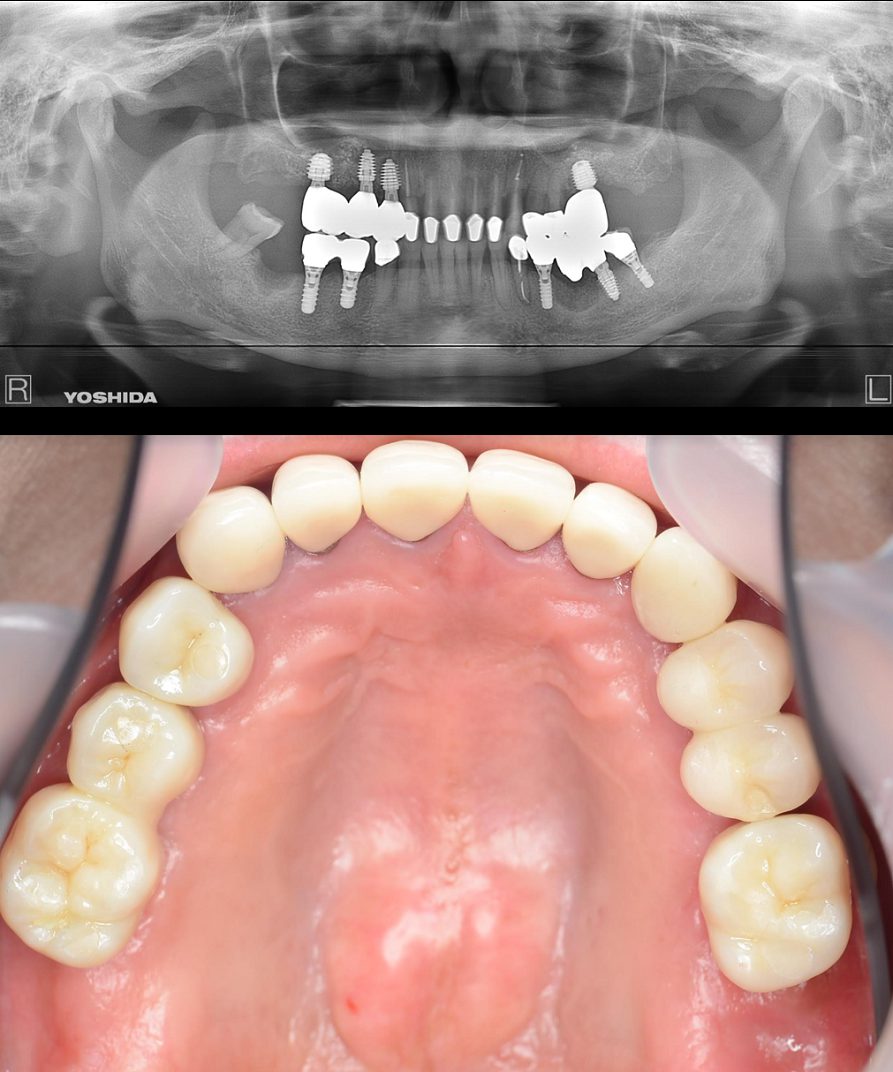

症例2【70代女性】主訴 義歯がわずらわしい・しっかり噛みたい

治療前

治療後(2年経過)

主訴 上顎のみ部分義歯を使用しているが、入れ歯が煩わしい、固定制のインプラントにして欲しいと来院。

左右上顎第一大臼歯相当は、骨の高さが不足しており、ソケットリフト(骨造成)の必要があり、左右第一小臼歯、第一大臼歯支台のインプラントブリッジを提案。

採血で得られた、CGFメンブレンとAFGブロック(人工骨β‐TCPとAFGを混ぜたブロック)を使用し骨を挙上し、インプラントを埋入。

右下のブリッジも、短根歯で動揺が激しい為に抜歯し、インプラント埋入。

上顎の免荷期間は約4ヶ月、下顎の免荷期間は約2ヶ月を経て、仮歯を装着、リハビリをし、メタルボンド(金属焼付ポーセレン)を装着。

費用 280万(オペ・ソケットリフト・人工骨・採血による濃縮血小板生成・仮歯・最終補綴物まで含む)